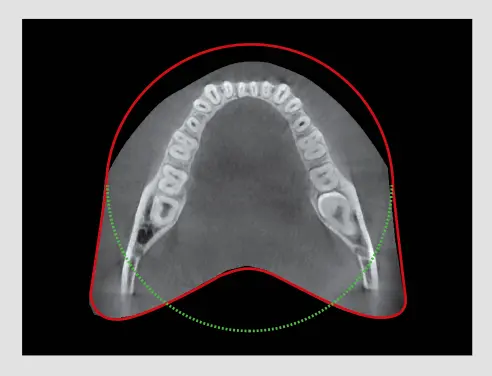

Extended Arch-Shaped FOV

The FOV of the A9 provides an arch-shaped volume, anatomically 9.3X8, showing a wider view of dentition when compared to other devices with the same 8X8 FOV. When the tooth is lying on its side, there is a high possibility that the tooth will be cut out of the image. This possibility is eliminated with our "arch-shaped volume" and shows the hidden dentition area.